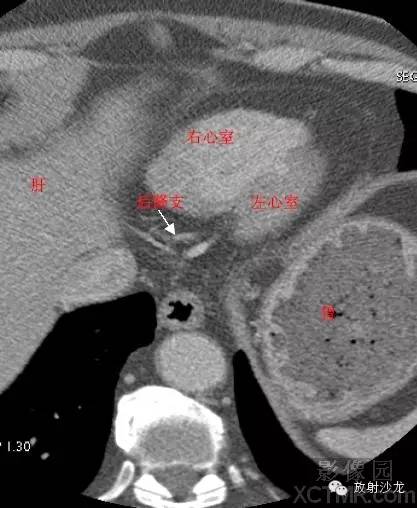

LV -Left Ventricle左心室

RV -Right Ventricle右心室

ConusBranch右动脉圆锥支